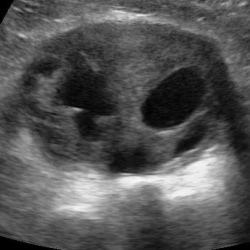

Выглядит забавно. Но это не прикол и не фотошоп) Мой коллега обнаружил. У кого какие мысли что это и где?